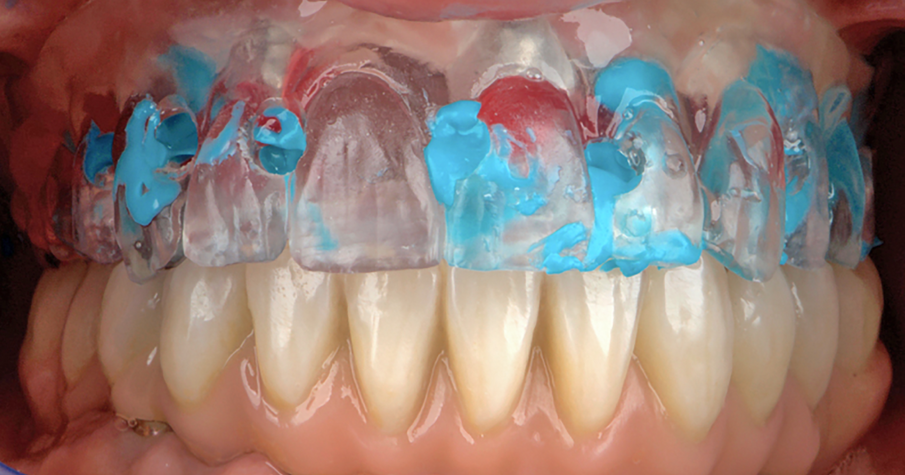

Dopo la rimozione dei denti residui e degli impianti, il paziente è stato immediatamente riabilitato con due protesi totali rimovibili diagnostiche in RP, che hanno migliorato i rapporti intermascellari, la VDO, OB, OJ, fonetica ed estetica. È stato eseguito un tracciato cefalometrico su una radiografia laterale del cranio per una valutazione funzionale iniziale del caso, seguita da una pianificazione protesica virtuale (Fig. 4), quindi radiologica (Fig. 5) e chirurgica. Le caratteristiche delle protesi studiate hanno determinato la pianificazione chirurgica (Smop, SwissMeda) (Fig. 6) e due guide chirurgiche sono state successivamente sinterizzate al laser (2Ingis) (Fig. 7). Gli impianti sono stati quindi posizionati come programmato (Figg. 8, 9), ad eccezione di quelli ai mascellari posteriori, dove è stato eseguito bilateralmente un grande rialzo del seno mascellare (Fig. 10).

L’ADSD e il Cad per il paziente sono stati quindi eseguiti a partire dalle foto e dai modelli virtuali che definivano il nuovo piano occlusale. Poiché gli impianti superiori non potevano essere caricati immediatamente, una mesostruttura avvitata di prova in alluminio è stata fresata al Cam per la sola mandibola, insieme a una ceratura preliminare, con denti singolarmente staccabili, per la rifinitura sequenziale (Fig. 17). I modelli con la ceratura preliminare fresata sono quindi stati trasferiti nuovamente sull’articolatore SL, ed essa è ulteriormente perfezionata dall’odontotecnico esperto, che ha modellato accuratamente le superfici funzionali secondo il modello di occlusione sequenziale ispirato a quello proposto dal Prof. Dr. R. Slavicek, con cere di diverso colore a evidenziare i rapporti di centrica, le funzioni di mediotrusiva e protrusiva, e le protezioni di retrusiva (Fig. 18). Sono stati controllati tutti gli aspetti dell’occlusione, le guide funzionali sequenziali e l’uniformità delle disclusioni (Fig. 19).